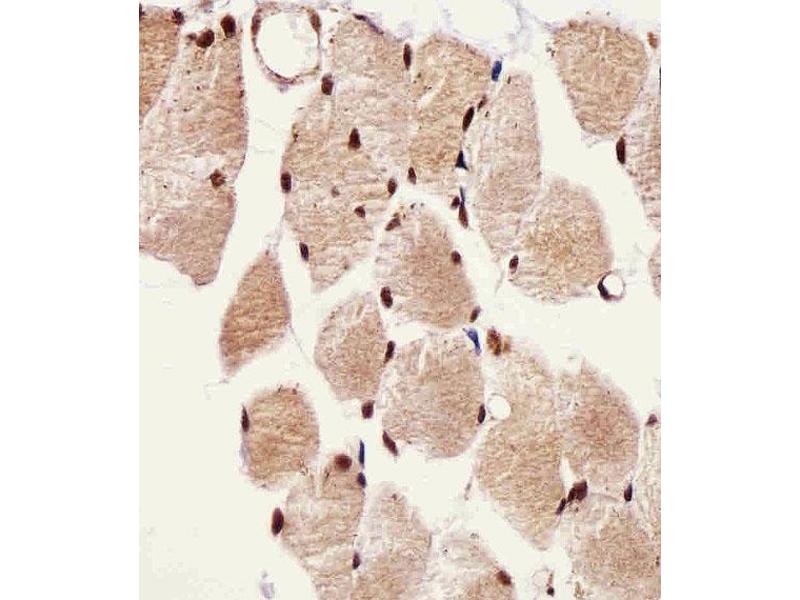

L’anticorps anti-SSNA1 Polyclonal Lapin est utilisé pour la détection de SSNA1 dans des échantillons de Humain. Il a été validé pour WB et IHC (p).

Western Blotting (WB), Immunohistochemistry (Paraffin-embedded Sections) (IHC (p))

This SSNA1 antibody is generated from rabbits immunized with a KLH conjugated synthetic peptide between 25-53 amino acids from the N-terminal region of human SSNA1.

WB: 1:1000. IHC-P: 1:25. IHC-P: 1:25